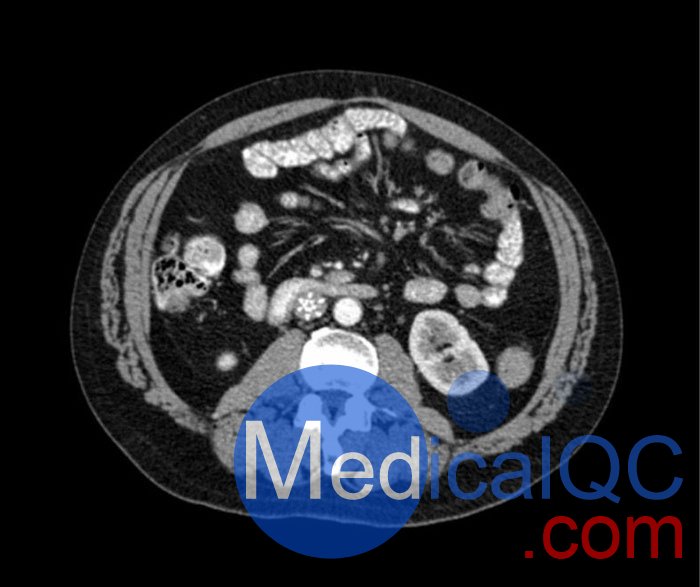

WEK53-04肝硬化腹部模體,WEK53-04腹部模體代表膽囊切除術(shù)后的腹部,帶有小夾子。肝臟有肝硬化的典型體征,在第三腰椎水平植入下腔靜脈過濾器。兩個腎臟都有囊性病變,左側(cè)有一小塊腎結(jié)石。

真實模擬脈管系統(tǒng)、骨骼和軟組織,包括肝臟、胰腺、脾臟、腎上腺、腎臟、胃、小腸和結(jié)腸。

• 肝硬化

• 膽囊切除術(shù)

• 下腔靜脈濾器

• 腎囊腫

• 腎結(jié)石

• 淋巴結(jié)腫大